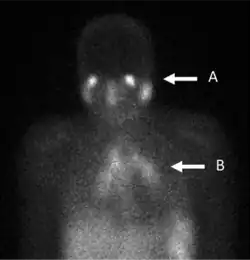

Gallium DOTA scans

68Ga DOTA conjugated peptides (including 68Ga DOTA-TATE, DOTA-TOC and DOTA-NOC) are used in positron emission tomography (PET) imaging of neuroendocrine tumours (NETs). The scan is similar to the SPECT octreotide scan in that an octreotide-based somatostatin analogue (such as edotreotide) is used as the radioligand, and there are similar indications and uses as octreotide scans, however image quality is significantly improved.[33] Somatostatin receptors are overexpressed in many NETs, so that the 68Ga DOTA conjugated peptide is preferentially taken up in these locations, and visualised on the scan.[34] As well as diagnosis and staging of NETs, 68Ga DOTA conjugated peptide imaging may be used for planning and dosimetry in preparation for lutetium-177 or yttrium-90 DOTA therapy.[35][36]

In June 2016, Netspot (kit for the preparation of gallium Ga-68 dotatate injection) was approved for medical use in the United States.[37][38]

In August 2019, 68Ga edotreotide injection (68Ga DOTATOC) was approved for medical use in the United States for use with PET imaging for the localization of somatostatin receptor positive neuroendocrine tumors (NETs) in adults and children.[39][40][41]

The U.S. Food and Drug Administration (FDA) approved 68Ga edotreotide (DOTATOC) based on evidence from three clinical trials (Trial 1/NCT#1619865, Trial 2/NCT#1869725, Trial 3/NCT#2441062) of 334 known or suspected neuro-endocrine tumors.[40] The trials were conducted in the United States.[40]